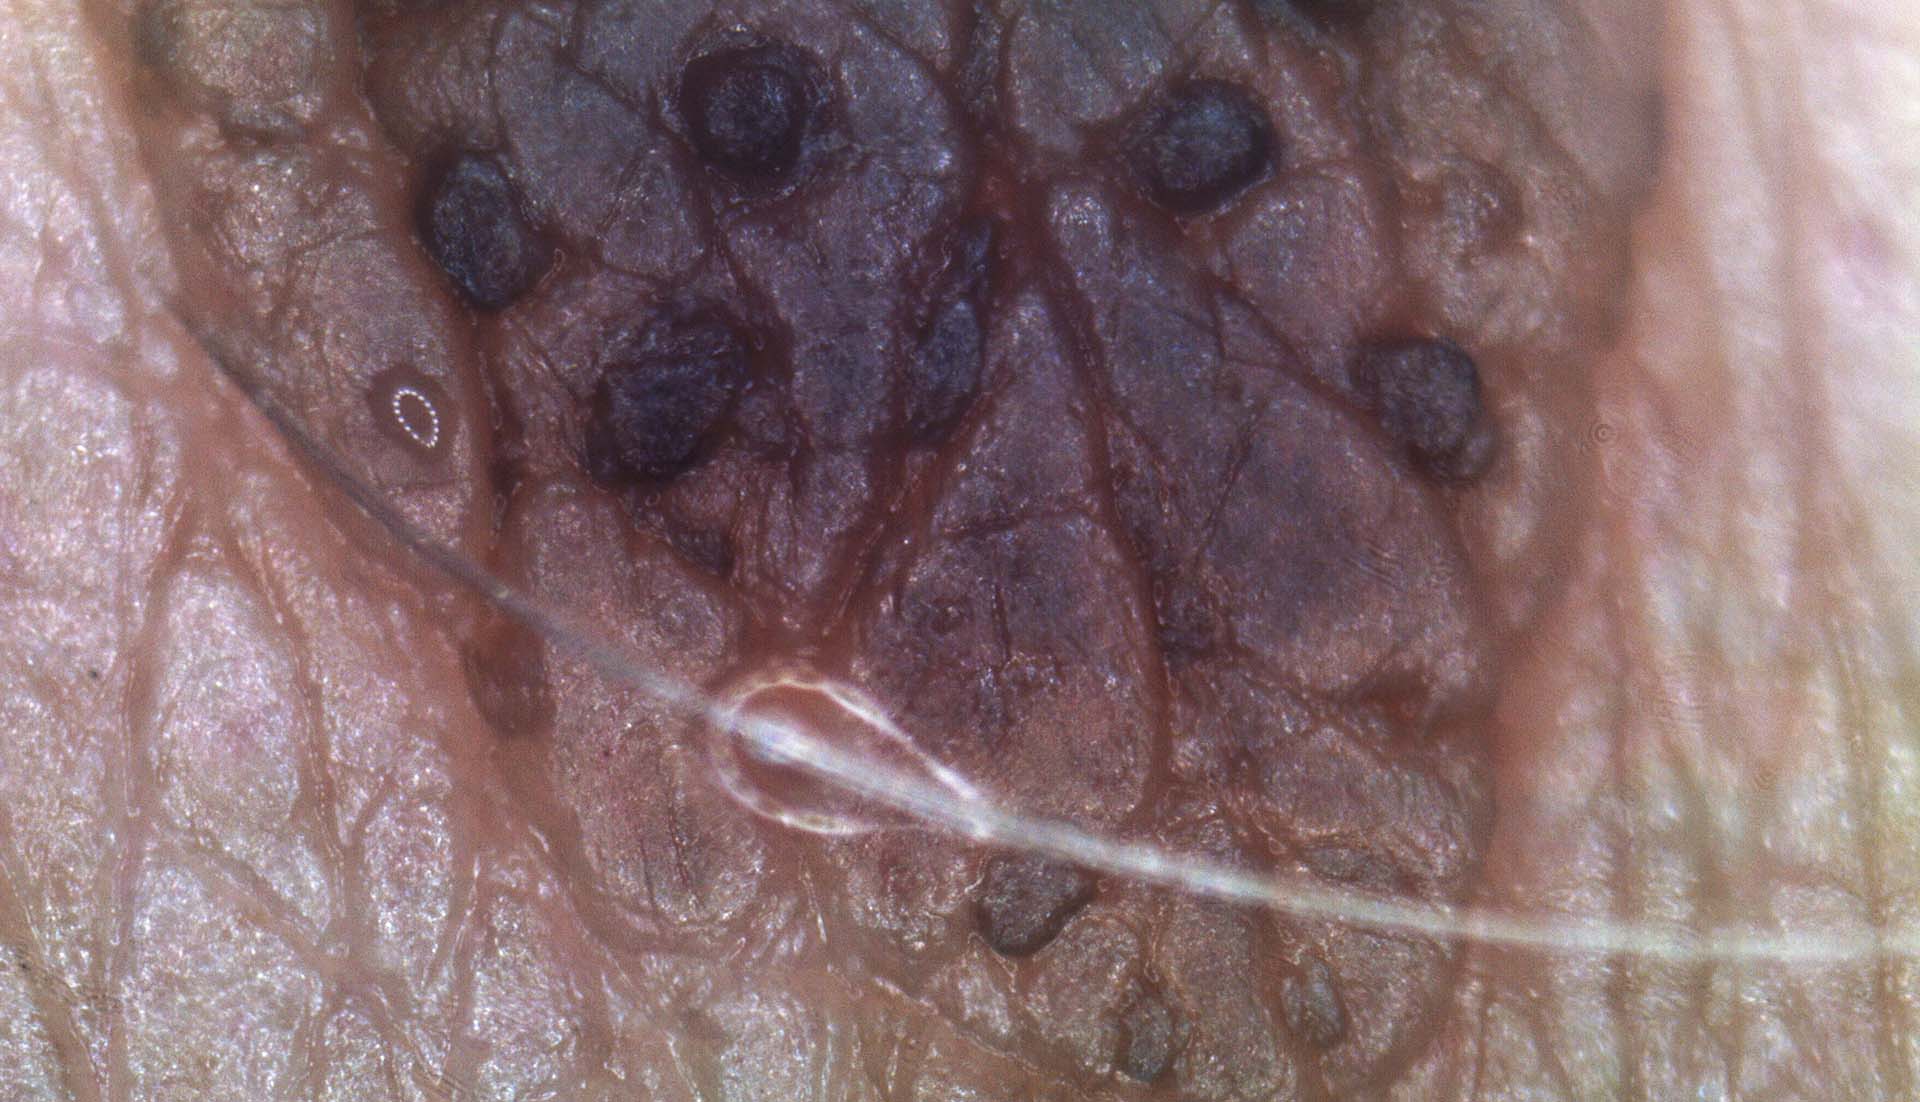

Segmentazione

La funzione di segmentazione determina il bordo della lesione i,dentificato da una curva di Jordan che separa l’area della lesione dallo sfondo.

La segmentazione manuale o automatica a seconda delle esigenze del clinico, segna il confine della lesione cutanea in tempo reale, rilevando il contorno della lesione, il suo centro, il suo orientamento e l’ellisse che si approssima all’intero neo.

Analisi

La funzione Segmentazione attiva l’analisi ABCDE su un’immagine di una lesione cutanea.

L’analisi ABCDE di IRSkin fornisce al medico informazioni quantitative riguardanti la morfologia e le caratteristiche pigmentarie della lesione cutanea.

Le funzioni di analisi ABCD, insieme alla possibilità di analizzare l’evoluzione di una lesione mediante la Body Map, forniscono informazioni quantitative e qualitative che possono aiutare il medico a migliorare la sua analisi ABCDE standard. Apparirà sullo schermo la schermata di analisi ABCD, insieme a i seguenti parametri numerici: